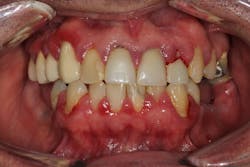

One reason people develop gummy smiles is inflammatory-induced gingival enlargement, typically caused by biofilm (bacteria) and the host response. Gum disease (gingivitis and periodontitis) can result in gum tissue swelling, redness, gum overgrowth, and bleeding (figure 1). In addition to bacterial infiltration of the gums due to poor oral hygiene, orthodontic appliances have been associated with gingival enlargement since braces can act as food traps (figure 2).Further reading: Considerations when using veneers to fabricate a perfect smile

- 50% of the cases are typically attributed to phenytoin (figure 3).

- 10% to 20% of the cases are typically attributed to calcium channel blockers, with nifedipine being the most notable problem (figures 4a and 4b).